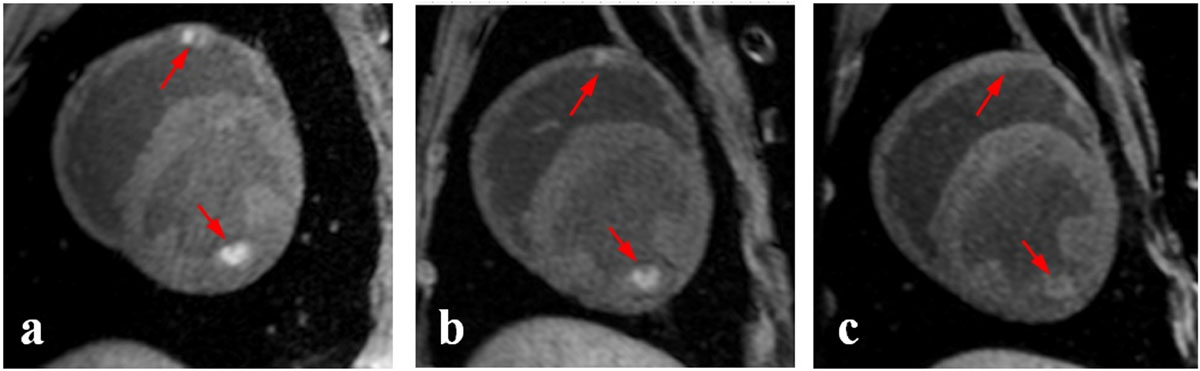

Representative T1w images of RF ablation lesions acquired acutely, 2, and 7 days post-ablation are shown in Figure 1. These images clearly demonstrate that visibility of ablation lesions in native T1w images drastically reduces few days after ablation. Quantitate analysis shown that both normalized lesion volume and IIR, decrease significantly (p < 0.05) as early as 2 days post-ablation (Figure 2). This trend continues further with time post-ablation, resulting in the inability to detect many ablation lesions on native T1w images acquired 7 days post-ablation.

Figure 1.

Representative T1w images of RF ablation lesions acquired (a) acutely, (b) 2 days post-ablation, and (c) 7 days post-ablation.